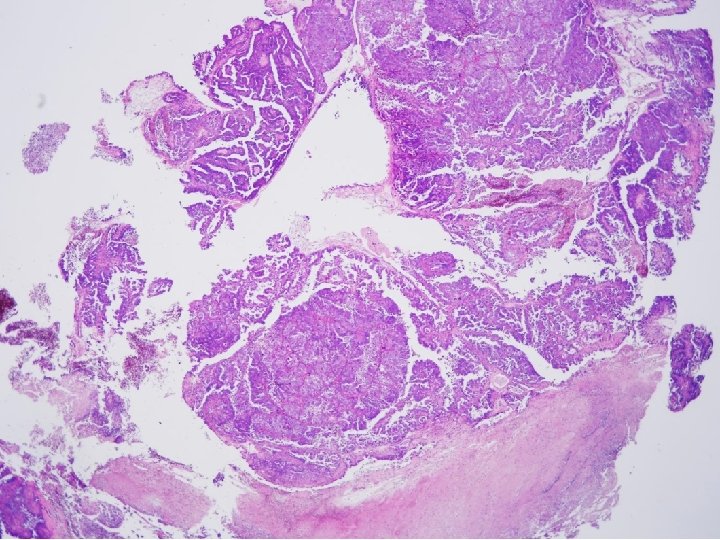

Tissue from uterine cervix, biopsy; Poorly differentiated adenocarcinoma with 1) sheets and papillary features 2) tubulocystic pattern 3) frequent clear cell feature c/w CLEAR CELL CARCINOMA

CYTOPATHOLOGIC FEATURES OF CLEAR CELL CARCINOMA • Arrangement – Cells are isolated, in loosely cohesive groups and in syncytial tissue fragments; hobnail pattern may be present • Cells – Medium to large with poorly defined cell borders; moderate to high N/C ratios; round, polygonal to hobnail type • Nuclei – Large, round, often eccentric, very pleomorphic; coarsely granular to smudgy chromatin; nucleoli are inconsistent; multinucleation • Cytoplasm – Variable, scant to abundant, clear to pale, weakly staining either eosinophilic or cyanophilic • Background – Clean, bloody or inflammatory; naked nuclei Color Atlas of DDx in Exfoliative and Aspiration Cytopathology, Kini